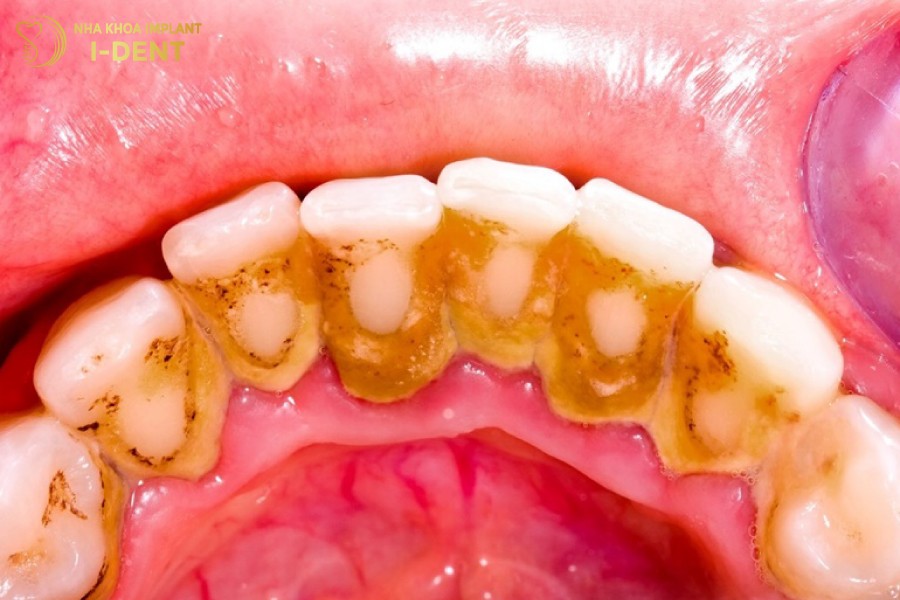

Tình trạng viêm tủy răng có mủ liên quan mật thiết đến vấn đề vệ sinh răng miệng. Khi mảng bám trên răng không được làm sạch sẽ tích tụ ngày càng nhiều, vi khuẩn có điều kiện sinh sôi tấn công gây hại cho răng. Men răng bị bào mòn, làm lộ ngà răng, tăng nguy cơ viêm nhiễm tủy răng.

Mảng bám vôi răng là nguyên nhân hàng đầu gây viêm tủy răng

- Cạo vôi răng để loại bỏ mảng bám, vi khuẩn gây hại.